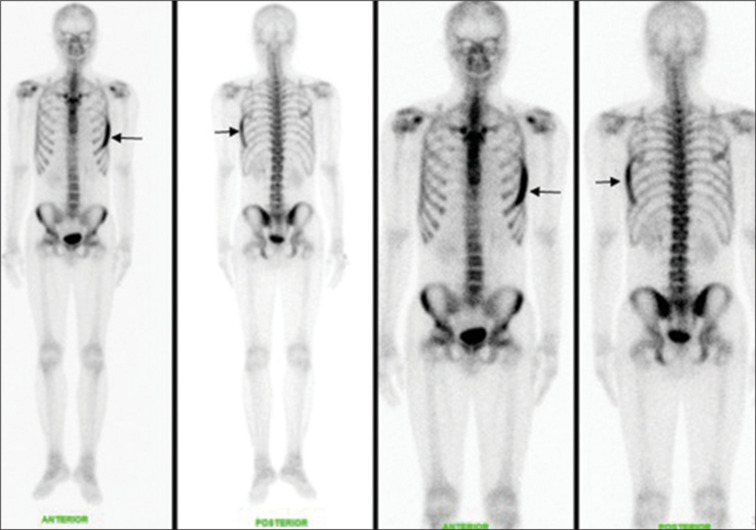

患者,37岁男性,最初表现为直肠出血。结肠镜检查显示直肠下部有圆周性病变,并伴有少量卫星性病变。当时,我们进行了活检,但组织病理学检查显示一致的孤立性直肠溃疡综合征。随后的骨扫描显示左侧第6肋骨的放射性示踪剂摄取增加,导致相应的单光子发射计算机断层扫描(SPECT)显示“香蕉样外观”和磨砂玻璃外观,与纤维发育不良相一致。鉴于其无症状状态,患者接受了关于其良性骨病变的安慰和监测。

The patient, a 37-year-old male, initially presented with per rectal bleed. Colonoscopy revealed a circumferential lesion within the lower rectum, along with a few satellite lesions. At that time, we performed a biopsy, but the histopathological examination revealed consistent solitary rectal ulcer syndrome. Subsequent bone scan revealed increased radiotracer uptake at the left 6th rib, resulting in a "banana-like appearance" and a ground glass appearance on the corresponding single-photon emission computed tomography (SPECT), in keeping with fibrous dysplasia. Given his asymptomatic state, the patient received reassurance and surveillance regarding his benign bone lesion.